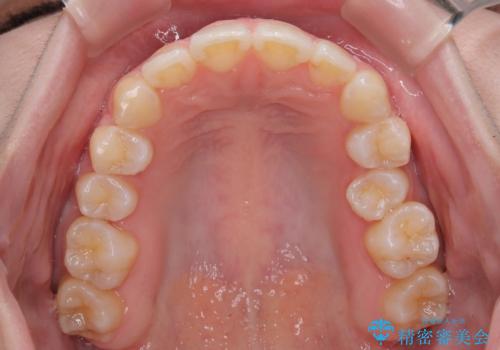

1年と少しで矯正治療を終えることができ患者様は大変満足されました。